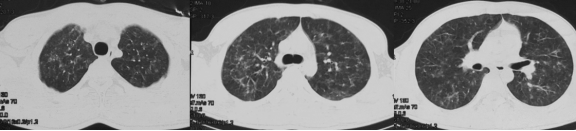

三种密度征(Three density pattern)里的三个区域分别是:高密度区提示磨玻璃影子,低密度区提示小气道疾病所累及的肺脏出现了气体陷闭的表现,还有一些正常的肺脏。

当出现三种密度征的时候,结合临床,能够高度提示这个患者是 HP。

这位慢性纤维化型过敏性肺炎患者就可以看到三种密度征、磨玻璃影、网格影、牵拉性支气管扩张,没有蜂窝。